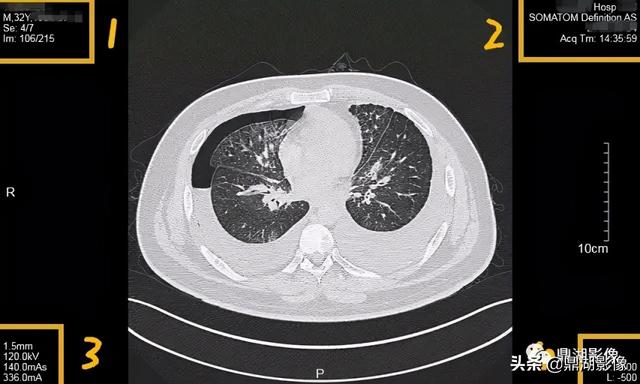

下图为另一个设备的CT片子

r和l哪个是左哪个是右,袜子r和l哪个是左哪个是右(竟然包含了这么多的信息)

我们看到这是另一个机器的DR图片信息

1区:IM为图像,106/215意为图中检查总共215张图片,SE为序列,此为第4个序列。

2区:所做检查医院名称,一般带有XX Hosptial或XX医院。

3区:扫描参数,CT的为扫描一序列的射线剂量,一般电压为120KV;图中信息:层厚1.5mm,管电压120KV,管电流量(mAs)140mAs,管电流(mA)。

需要指出:

eff.mAs:有效mAs,是实时变化的

ref.mAs:标准mAs,是不变的

4区:为显示视野。